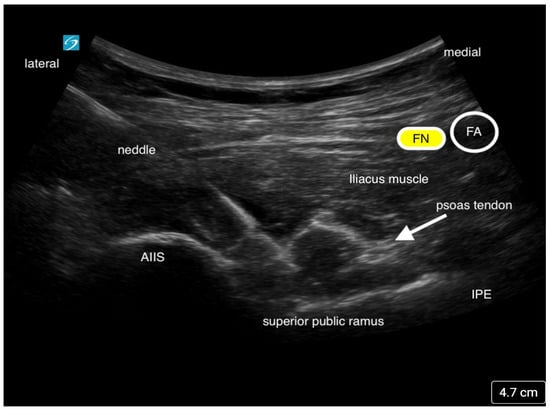

The Pericapsular Nerve Group (PENG) block is a fascial plane block that was developed by Giron-Arango et al. at Toronto Western Hospital and the University of Toronto to block the high articular branches of the femoral (FN), obturator (ON), and accessory obturator nerves (AON) to the hip joint [23]. These branches are mostly responsible for the nociceptive pain in the anterior and superolateral capsule of the hip joint. The FN and AON are often found between the anterior inferior iliac spine (AIIS) and the iliopubic eminence (IPE), thus making it easier to target both nerves. The block is performed with the patient in the supine position. Local anesthetic is deposited using a curvilinear low-frequency ultrasound probe with an in-plane technique from lateral to medial. The needle tip is placed in the fascial plane between the psoas tendon and the ilium (Figure 6) [23,24]. As described by Giron-Arango and colleagues, an optimal ultrasound image should include the AIIS, IPE, psoas tendon, iliopsoas muscle, and more superficially, the femoral neurovascular bundle [23]. Typically, 10–20 mL of local anesthetic is adequate to provide effective analgesia if there is fluid spread along the plane displacing the psoas muscle tendon.

Figure 6. This is an ultrasound image of the Pericapsular Nerve Group Block (PENG). Local anesthetic is injected below the psoas tendon. The needle approach is from lateral to medial. The femoral nerve (FN) and femoral artery (FA) is seen medially.